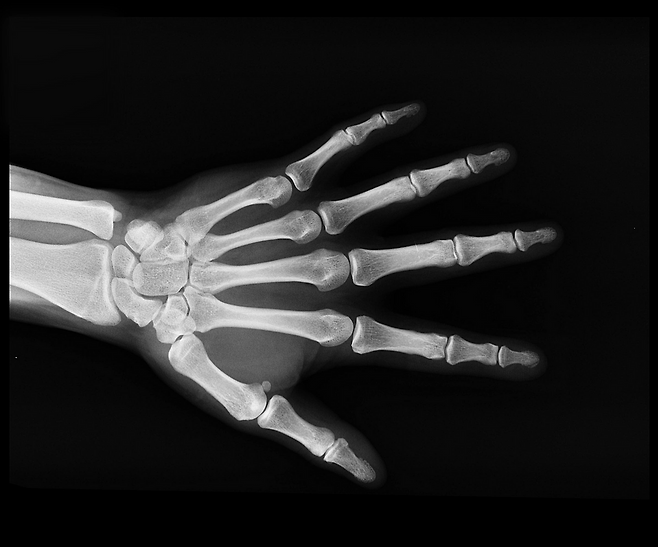

많은 사람들이 손 저림을 단순히 혈액순환 부족으로 오해합니다. 하지만 만성적으로 지속된다면 신경계에 이상이 있다는 경고일 수 있습니다.

대표적인 원인 중 하나는 비타민 B군 부족입니다. 특히 비타민 B1(티아민), B6(피리독신), B12(코발라민)이 부족할 경우, 말초신경염이나 신경전달 이상이 생겨 손발 저림, 감각 이상 증상이 나타납니다.